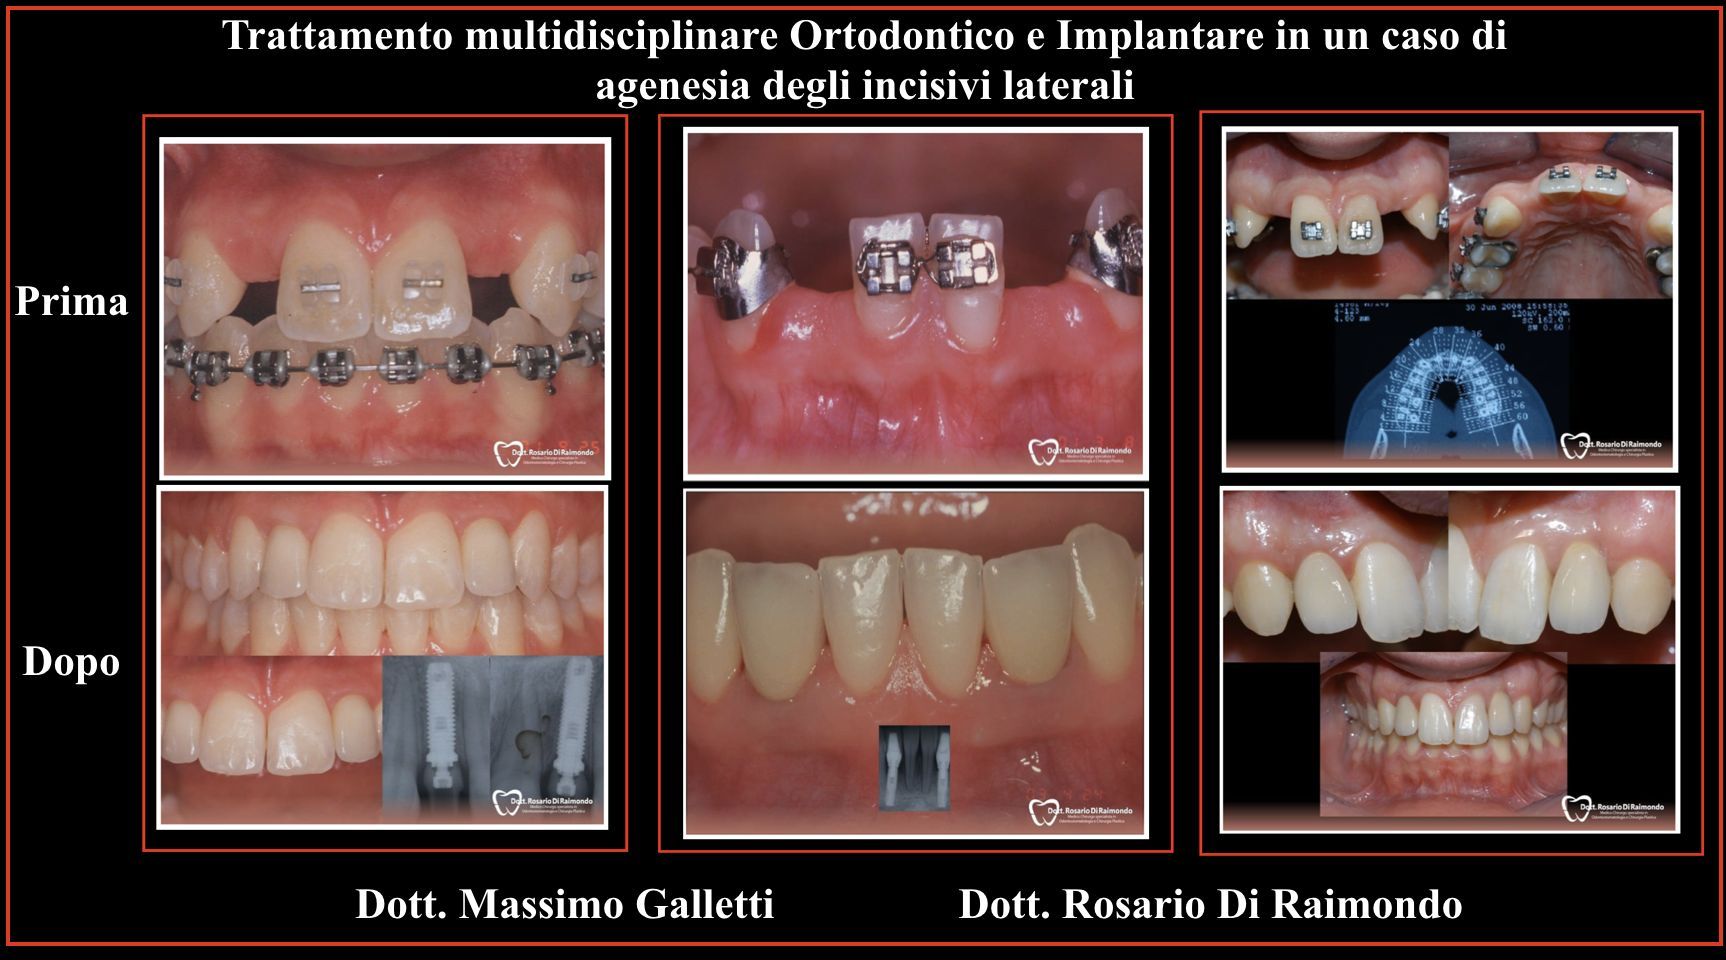

Le classiche indicazioni dell’uso degli impianti dentali sono: edentulia parziale (mancanza di uno e più denti), edentulia totale (mancanza totale degli elementi dentali di una o entrambe le arcate), e i casi di agenesia (mancanza di denti dalla nascita).

Casi Trattati

Di seguito riportiamo alcune fotografie di casi di Implantologia già trattati.